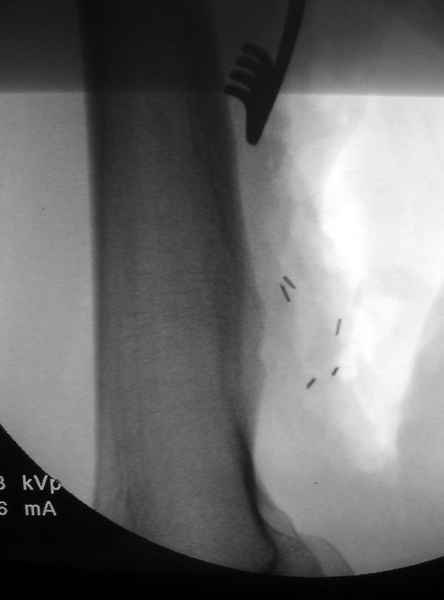

Пару лет назад наблюдал больную 35 лет, физически

здоровую, отслужила в Ираке, жаловалась на слабость в конечности во время физических нагрузок.

Ангиография подтвердила васкулярную аневризму в

результате давления экзостозом. Совместно с сосудистым хирургом была проведена плоскостная резекция с дальнейщим восстановлением сосуда венозным графтом.